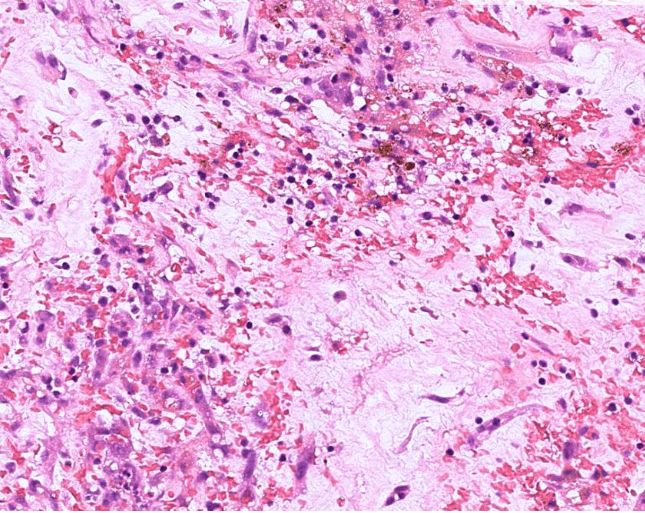

colon cancer